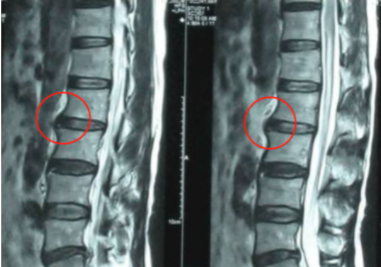

医生听了我的描述和初步症状诊断后怀疑我是腰椎间盘突出,随后让我去做了ct,结果显示就是腰椎间盘突出。医生表示目前作为一个阶段性发作的状态,疼痛以及酸胀感会比较明显,建议我尽快治疗。后来在医生的帮助下,仅仅21天,我就恢复了健康。下面是我个人治疗经历分享,希望可以帮助到大家!